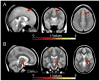

Effective adaptation to the demands of a changing environment requires flexible cognitive control. The medial and the lateral frontal cortices are involved in such control processes, putatively in close interplay with the BG. In particular, dopaminergic projections from the midbrain (i.e., from the substantia nigra [SN] and the ventral tegmental area) have been proposed to play a pivotal role in modulating the activity in these areas for cognitive control purposes. In that dopaminergic involvement has been strongly implicated in reinforcement learning, these ideas suggest functional links between reinforcement learning, where the outcome of actions shapes behavior over time, and cognitive control in a more general context, where no direct reward is involved. Here, we provide evidence from functional MRI in humans that activity in the SN predicts systematic subsequent trial-to-trial RT prolongations that are thought to reflect cognitive control in a stop-signal paradigm. In particular, variations in the activity level of the SN in one trial predicted the degree of RT prolongation on the subsequent trial, consistent with a modulating output signal from the SN being involved in enhancing cognitive control. This link between SN activity and subsequent behavioral adjustments lends support to theoretical accounts that propose dopaminergic control signals that shape behavior both in the presence and in the absence of direct reward. This SN-based modulatory mechanism is presumably mediated via a wider network that determines response speed in this task, including frontal and parietal control regions, along with the BG and the associated subthalamic nucleus.